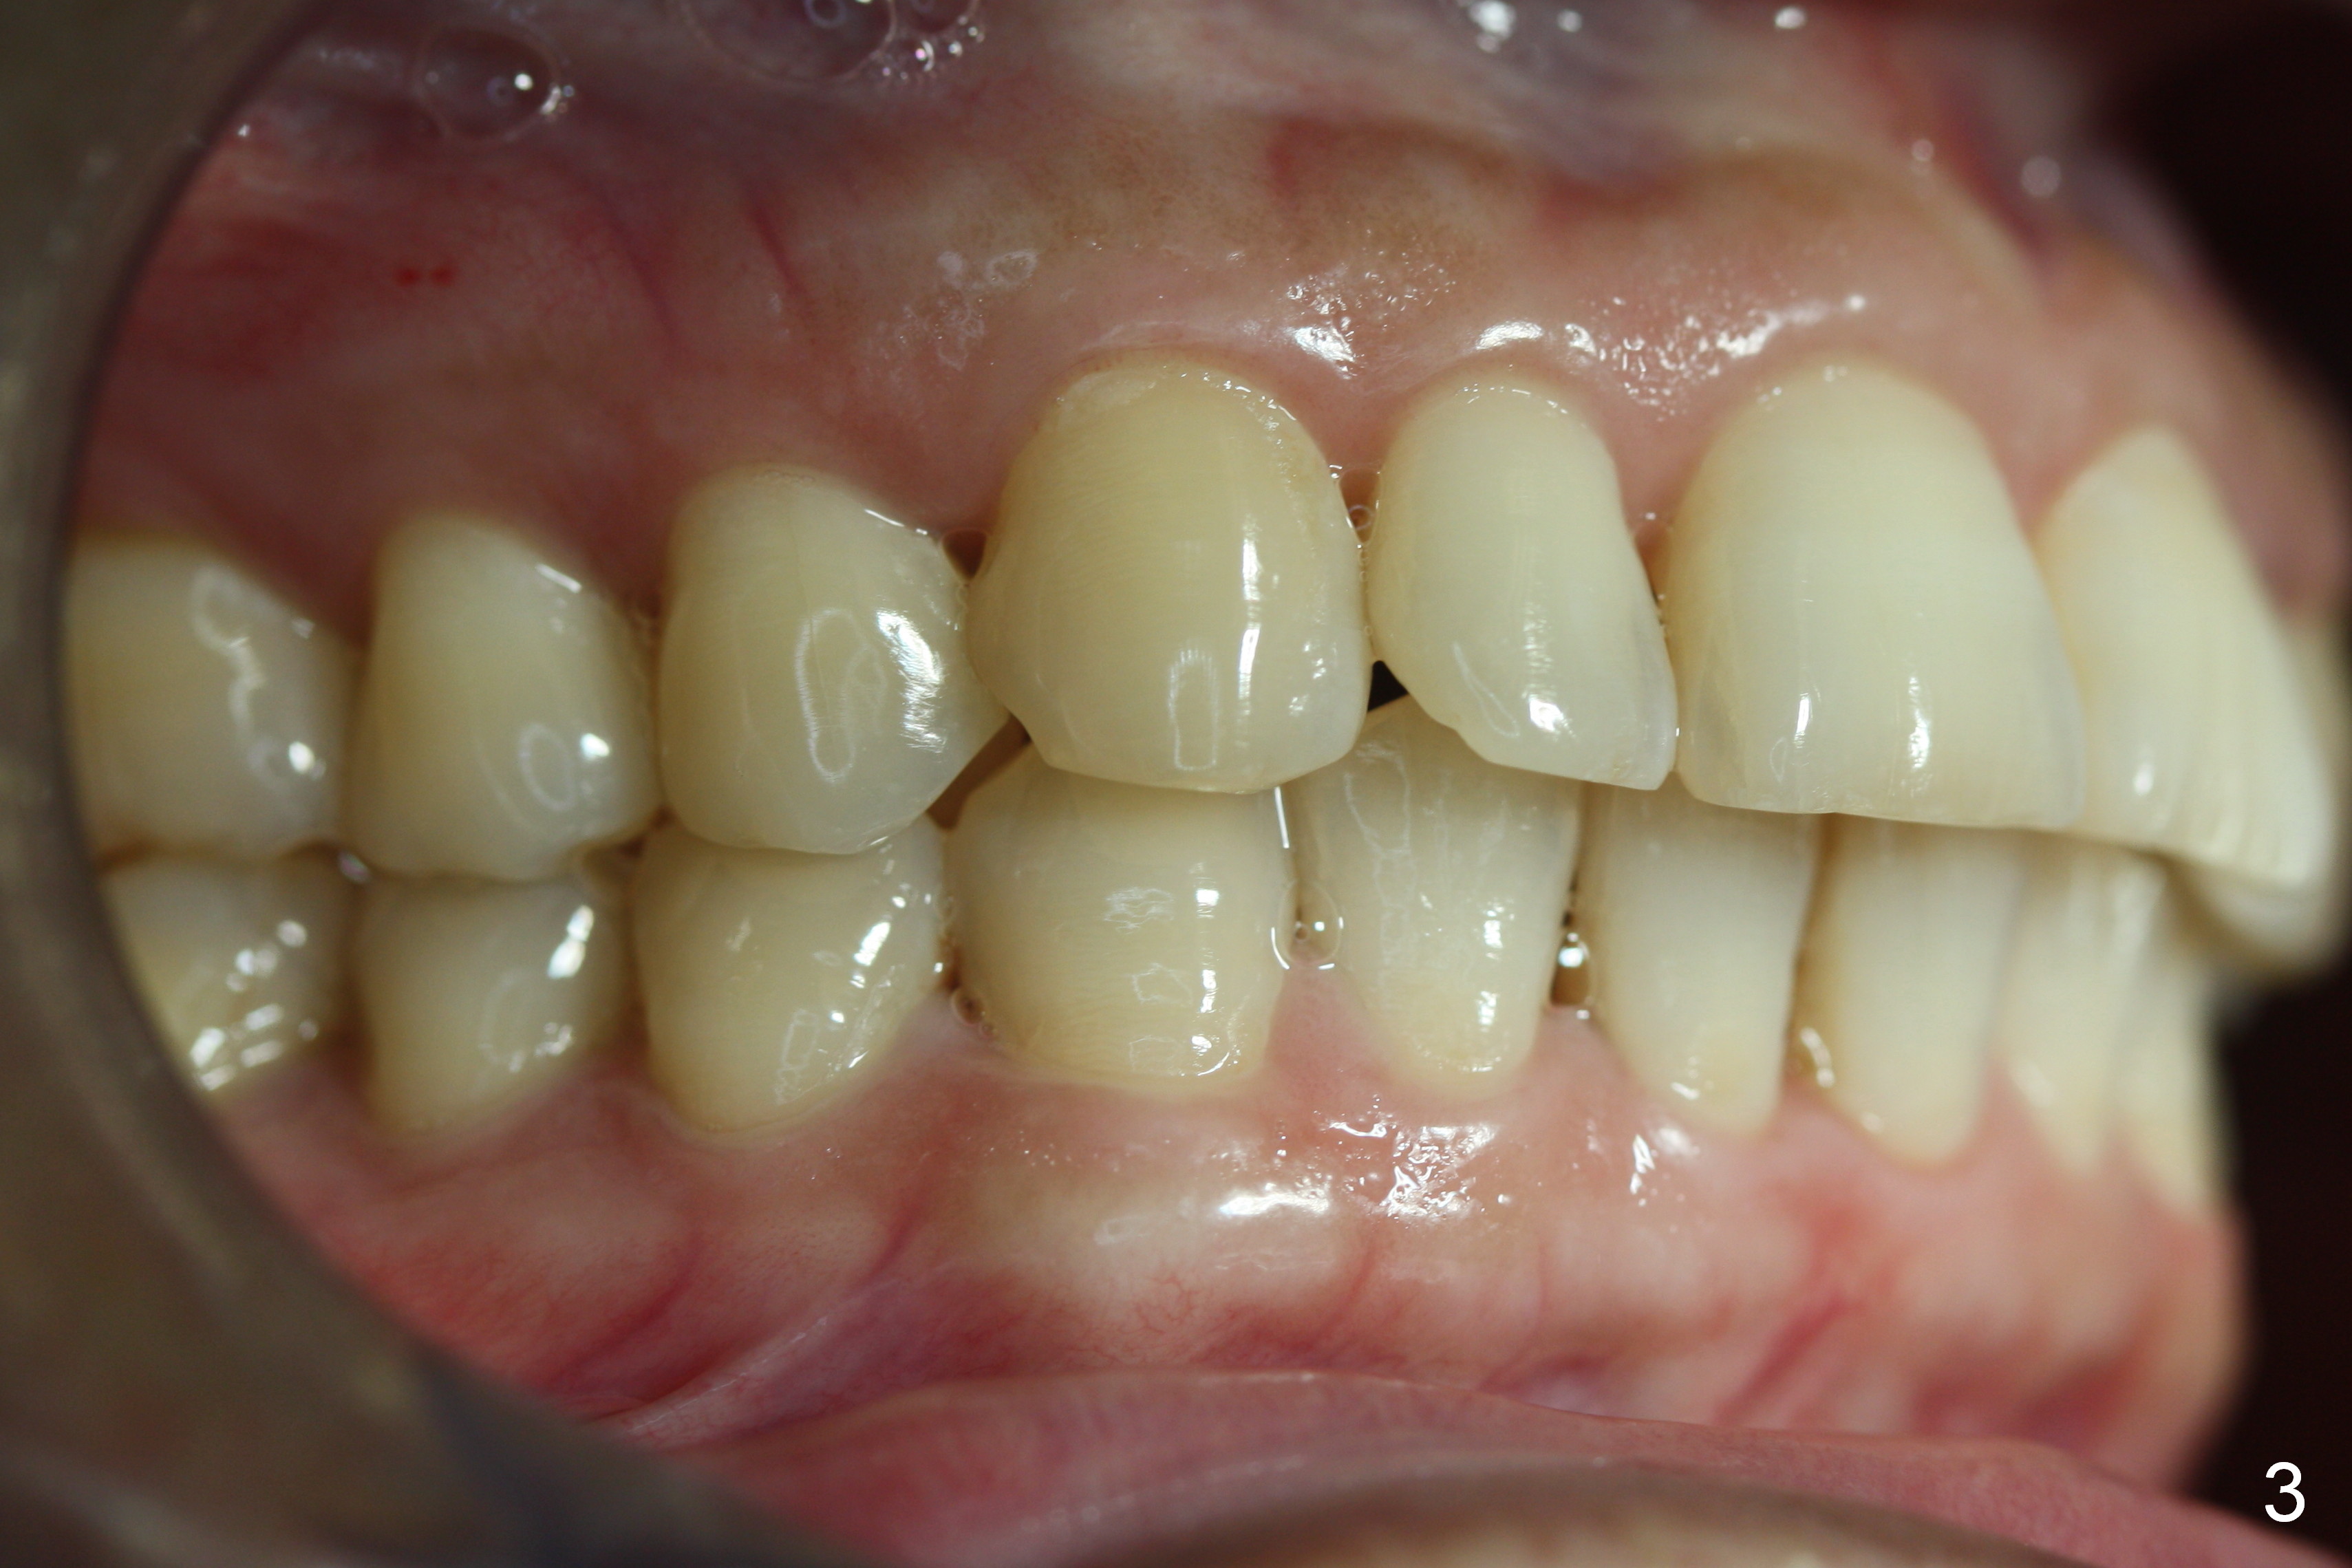

A 53-year-old woman wants to improve tooth appearance. Her concerns include microdontia at UR, UL 2 and caries at UL 3. The upper dental midline deviates to the left (Fig.1), while the lower one to the right (Fig.2). This may be related to unilateral Class II malocclusion (Fig.3,4).

What has been done is arch wire sequence, proximal reduction and move the upper right teeth to the right (Fig.5) and the lower left teeth to the left (Fig.6) sequentially. It may be not enough when the unilateral Class II malocclusion is not addressed directly. Pay attention to the present occlusion now and address properly.